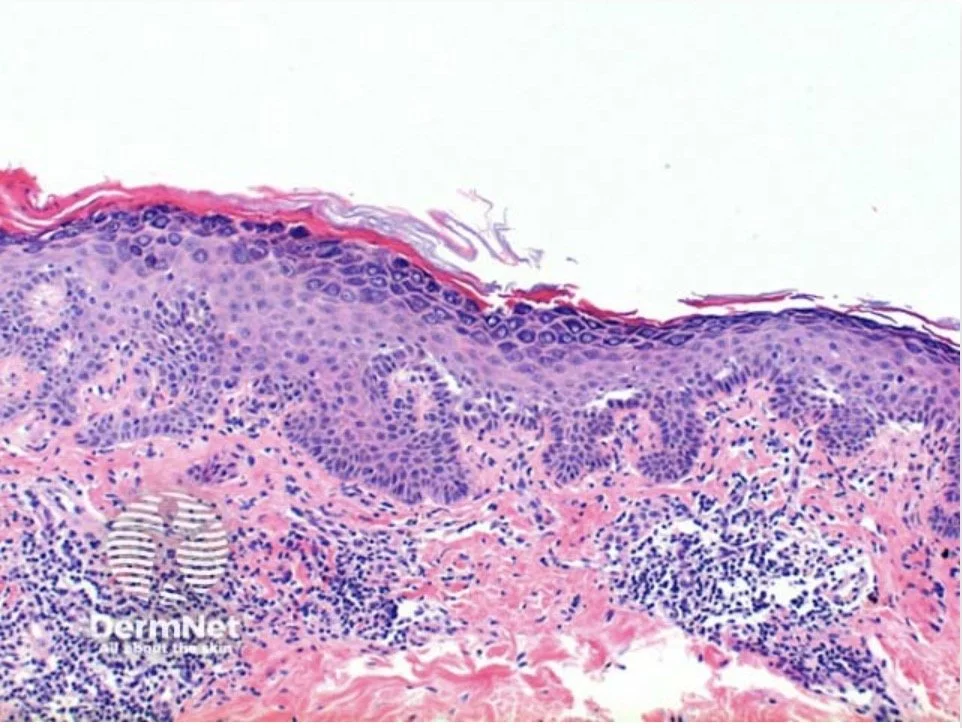

Pemphigus diseases (superficial):

• Antibodies bind to keratinocytes

• Forms a 'chicken wire pattern'

• Intercellular deposition of IgG +/- C3

Dermnet- https://dermnetnz.org/topics/pemphigus-vulgaris-pathology/

Pemphigus is a group of autoimmune bullous diseases primarily affecting the skin and/or mucous membranes, charachterised by antibody-mediated acantholysis

Acantholysis refers to the separation of keratinocytes due to disruption of intercellular bridges (desmosomes)

The acantholysis in PV occurs just above the basal layer of the epidermis, leading to a suprabasilar split